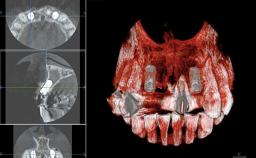

A 38-year-old woman presented with an esthetically unacceptable fixed partial denture replacing teeth 11, 21, 22. She had lost these teeth due to trauma when she was a child. The patient was not in pain but very concerned based on her previous experience that dental treatments had never satisfied her esthetic expectations. She was in good general health and reported no regular medications. No periodontal disease was noted despite the fact that the buccal flange of the prosthesis impeded cleaning of the tooth abutments. The patient did not smoke and complied with home maintenance requirements, as evidenced by her good oral hygiene status.

Bone Augmentation | Horizontal|Simultaneous|Staged |

Augmentation Materials | Autogenous block(s)|Xenogenous|Membrane |

Bone Volume | Deficient horizontally, requiring prior grafting |